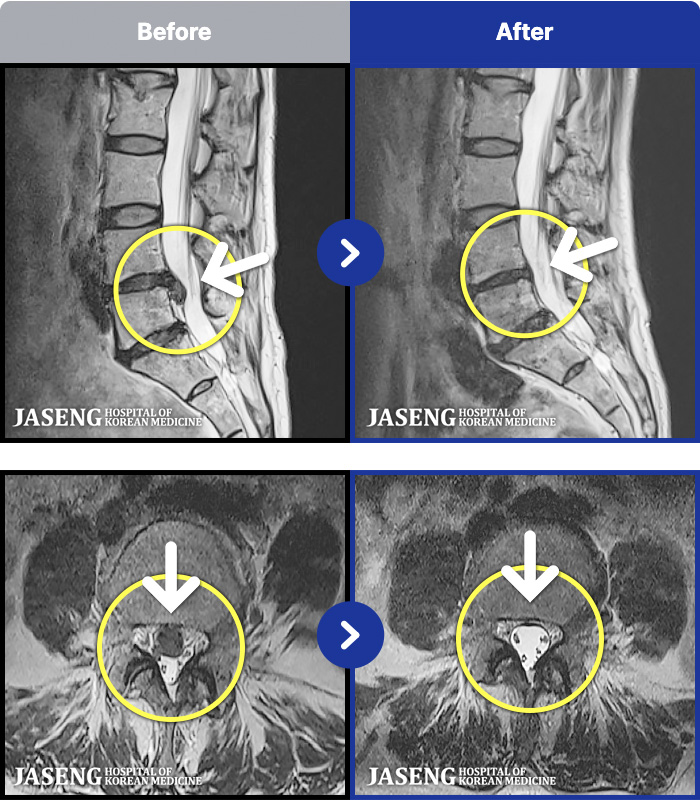

54 MRI ũ ʸ Ȯϼ.

ȯںп Ǹ ǿ ԿǾ, ο ġ ۿ Ƿ ġḦ Ͻñ ٶϴ.